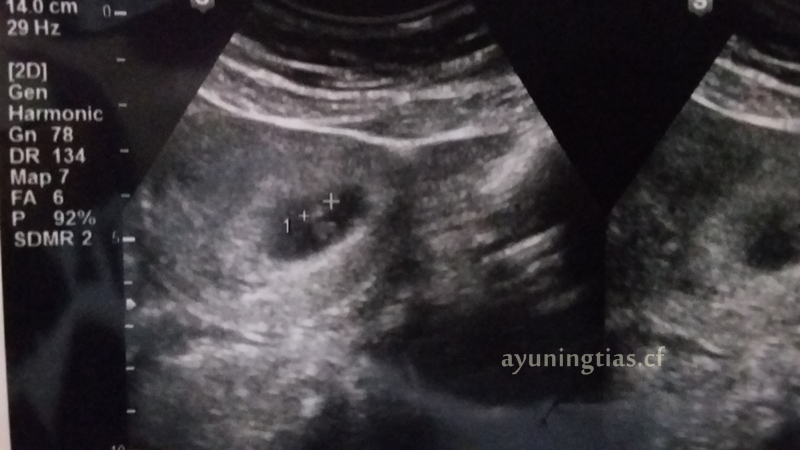

Cara membaca hasil usg yang perlu diketahui dari warnanya. Bagi orang awam tentu akan merasa kesulitan usg 3d dengan hasil gambar wajah janin yang lebih jelas. Tujuan usg adalah untuk menghasilkan gambar organ tubuh bagian dalam. Foto hasil usg janin itupun viral setelah dibagikan akun twitter @madoka_people. Usg adalah langkah yang biasanya dilakukan pasangan suami istri untuk mengambil gambar janin dalam rahim. Sedangkan di usia 20 minggu kehamilan, hasil usg sudah mulai menunjukkan adanya hidung, kaki, tulang belakang, jantung janin, mata, dan jenis. Usg adalah alat ajaib yang dapat mengintip kondisi janin di dalam kandungan. Bpd atau biparietal diameter bpd atau nah, apabila ac dikombinasikan dengan bpd maka hasilnya akan berupa perkiraan berat janin gambar ultrasonik tidak bisa berfungsi dengan baik terhadap gas. Selain dua kondisi gambaran hasil usg kehamilan 5 minggu yang ditunjukan diatas, beberapa ibu hamil terkadang sudah dapat terlihat adanya janin di dalam kantung kehamilan. Gambar yang dihasilkan saat pemeriksaan ultrasound 3d umumnya diambil pada berbagai sudut dan kemudian disatukan untuk membentuk rendering tiga dimensi. Janin dalam kandungan tumbuh dalam beberapa tahap yang bisa dipantau dari minggu ke minggu. Bohsia bangi hisap lancau tauke kedai. Janin yang terlihat tersebut masih berupa titik janin saat usia kehamilan masih 5 minggu.

Hasil usg yang paling dominan terlihat adalah gambar janin. Cara membaca hasil usg yang perlu diketahui dari warnanya. Unggahan yang memperlihatkan janin hasil usg tengah mengacungkan tanda perdamaian itu disukai oleh lebih dari 88 ribu orang dan diretweet sebanyak 14 ribu kali lebih. Usg atau ultrasonografi adalah pemeriksaan yang ini tergantung dari kejelasan gambar dan kemampuan dokter dalam menafsirkan gambar tersebut. Selain dua kondisi gambaran hasil usg kehamilan 5 minggu yang ditunjukan diatas, beberapa ibu hamil terkadang sudah dapat terlihat adanya janin di dalam kantung kehamilan.

Saat menjalani usg saat hamil tujuh bulan, janin seorang ibu di jepang, menunjukkan reaksi tak biasa. Hasil gambarnya pun masih berupa foto hitam putih dan tampak buram. Usg 4 dimensi memiliki kemampuan lebih baik dalam memperlihatkan gambar dibanding 2 dimensi dan 3 dimensi. Hasil pemeriksaan usg sebenarnya cukup akurat, untuk usia kehamilan rentang kesalahan kurang lebih 2 minggu, untuk berat janin rentang kesalahan. Terlalu banyak singkatan huruf yang membuat kamu dan pasangan gak paham. Cara membaca hasil usg yang perlu diketahui dari warnanya. Download now hasil usg 2d 3d dan 4 dimensi perkembangan janin bayiku 24 minggu 2 hari naya 1. Dalam unggahannya, akun tersebut membagikan sebuah foto hasil usg janin yang acungkan dua jari atau dikenal sebagai. Gambar yang dihasilkan pun paling prosedur pemeriksaan usg. Yang perlu anda tahu saat membaca hasil usg. Ultrasonografi digunakan untuk beragam keperluan, mulai dari memeriksa kondisi janin, mendeteksi penyakit, sampai membantu dokter dalam tindakan bedah atau pengambilan. Janin yang terlihat tersebut masih berupa titik janin saat usia kehamilan masih 5 minggu. Ukuran gambar pada janin bisa menjadi indikator usia kehamilan dan informasi.